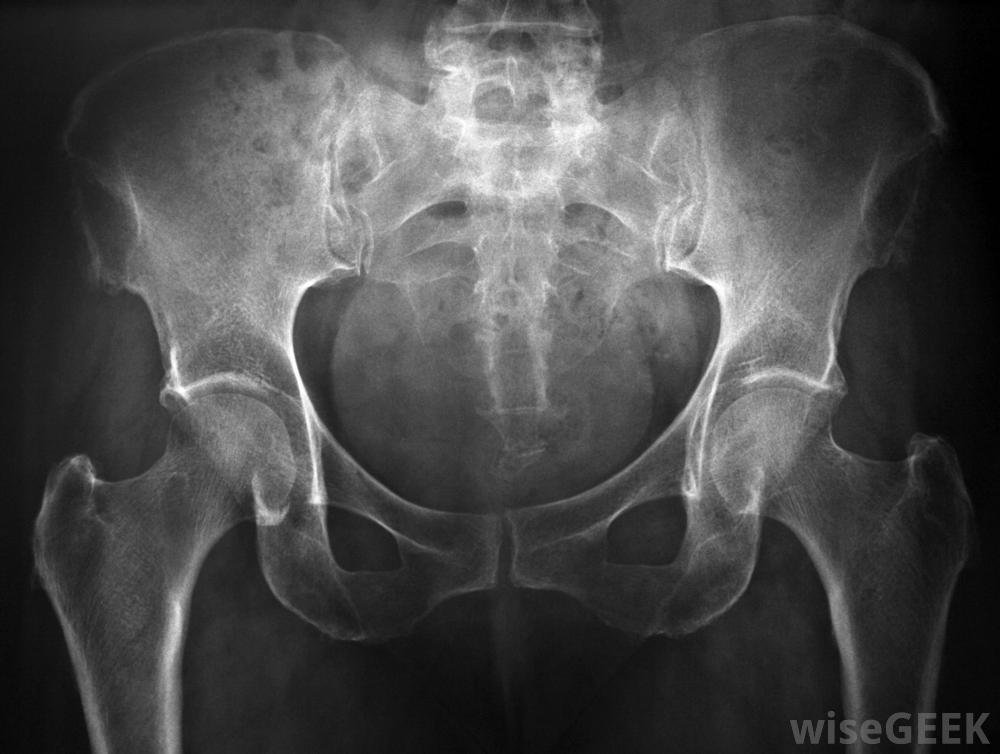

髖關節窩的外緣襯有一層軟骨組織,稱為下唇。下唇有助于減少關節摩擦并提供穩定性。如果由于運動損傷、摔倒或關節炎等退行性疾病導致唇部撕裂,個體可能會感到明顯的疼痛、腫脹,輕微的髖部唇撕裂可以通過消炎藥、休息、冰敷和柔韌性鍛煉來治療。嚴重的撕裂通常需要手術修復唇,并進行后續的物理治療以恢復力量和穩定性髖關節的X光片有助于顯示軟骨損傷的嚴重程度。在大多數情況下,髖關節唇撕裂是由于髖關節窩受到直接損傷而發生的。接觸時撕裂是常見的像足球這樣的運動以及直接掉在關節上的意外事故,尤其是在關節超出正常活動范圍甚至完全脫臼的事故中更是如此。在高爾夫和田徑比賽中重復使用臀部也會導致陰唇撕裂骨或軟骨疾病,如股骨髖臼撞擊(FAI)和關節炎患者有發生髖部問題的風險。OTC止痛藥可以幫助髖部唇部撕裂一個人遭受輕微的髖關節唇撕裂,通常會感到疼痛、腫脹和關節僵硬。髖關節可能會持續疼痛,觸感柔軟,失去柔韌性會使站立時腿部難以承受重量。如果是嚴重的損傷,唇完全撕裂,則會感到疼痛通常是鋒利的,難以忍受的。一個人可能會感到惡心,并且發現腿上無法承受任何重量。醫學評估對于確定損傷的嚴重程度和治療方案非常重要。拐杖可能髖部唇裂后需要。醫生通常通過感覺關節和進行診斷測試來檢查髖部唇裂,例如X光和核磁共振成像(MRI)掃描。X光和MRI結果可以讓醫生清楚地了解軟骨損傷的嚴重程度。如果唇部部分撕裂,患者會被指示避免活動,并每天對關節進行幾次冰敷。他或她可能會配備一個拐杖來幫助減輕壓力醫生通常建議加強鍛煉,服用非處方藥(OTC)來進一步減輕腫脹。如果治療一個月后,淚液疼痛沒有好轉,或者撕裂特別嚴重,通常需要一種稱為髖關節鏡的手術在手術過程中,外科醫生會在臀部一側做一個小切口,插入一個微型攝像機觀察軟骨損傷,然后用一把小手術刀切除惡化的組織,然后醫生把陰唇縫合起來。髖關節鏡檢查后,通常需要進行物理治療,以重建關節的力量并恢復關節的柔韌性。愈合時間可能會有所不同,但大多數患者在六個月后就可以恢復手術。核磁共振掃描可以確認髖關節唇撕裂的診斷。